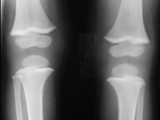

Rickets-both knees

Rickets-both knees